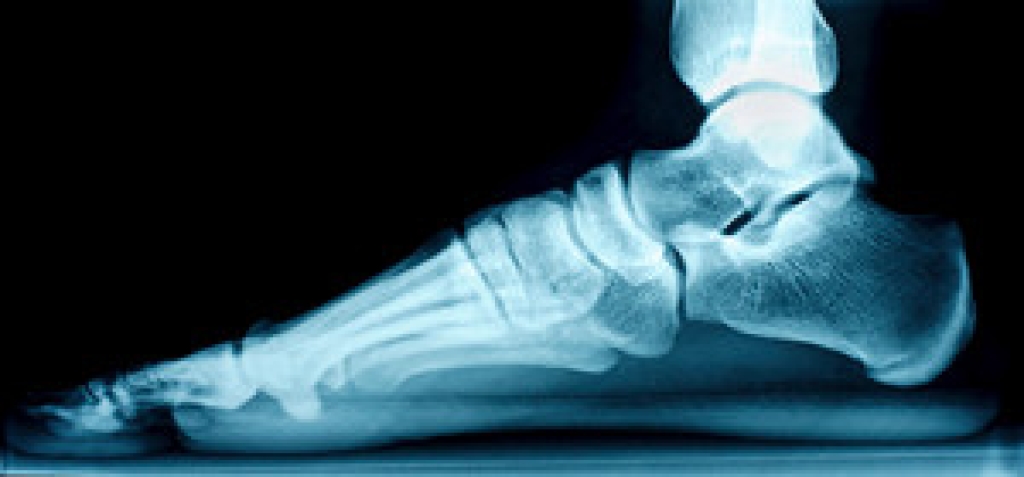

Flat feet is a condition in which the arch, the curved middle part of the bottom of the foot, is absent or has collapsed. The lack of an arch causes the entire sole of the foot to make direct contact with the ground when walking or standing. There are actually two types of flat feet that differ slightly from one another. Flexible flat feet have the ability to form an arch, but this arch flattens when any weight is put on the foot. However, the arch is visible when you are sitting down or holding your foot up in the air. This is the most common type of flat foot. Rigid flat feet cannot form an arch, regardless of whether or not weight is placed on them. While most cases of flat foot do not require medical intervention, sometimes this condition can cause pain or discomfort. In those cases, it is recommended that you see a podiatrist for treatment.

Flatfoot is a condition in which the arch of the foot is depressed and the sole of the foot is almost completely in contact with the ground. About 20-30% of the population generally has flat feet because their arches never formed during growth.